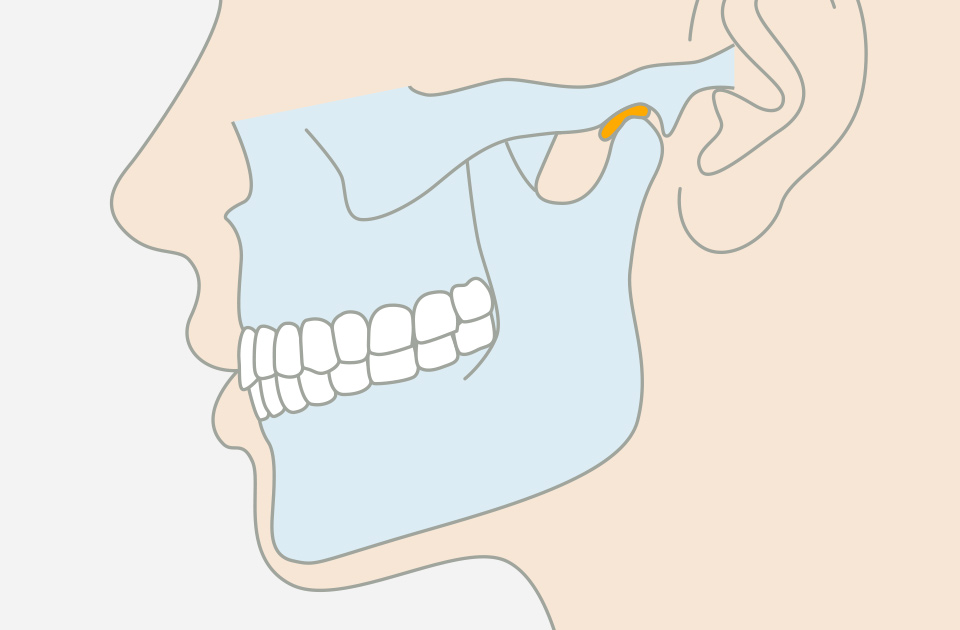

咬み合わせ外来

歯だけではなく、顎、骨、筋肉が正しく機能することで健康的に噛むことが可能になります。咬み合わせを修正することは呼吸や全身のバランスの改善にも繋がります。おかしな筋肉の使い方は顎関節症などのトラブルを招くため、骨格から口腔環境を整えます。

関節の

位置

顎の関節が正常な位置にある

顎の関節の位置にズレがなく、顎関節と歯のバランスの調和が取れている。